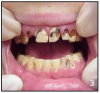

The use of MA has a pattern of damage in the mouth. There are several factors when combined that create an environment that destroys the teeth, the blood supply and supporting tissues. Figures 3 and 4 show two examples of oral destruction MA use can cause.

Figures 3 and 4 Rampant Decay – Photos courtesy of: Sharlee Shirley, RDH, MPH; Jim Cecil, DMD, MPH, University of Kentucky, School of Dentistry United States Department of Justice Meth Awareness Program